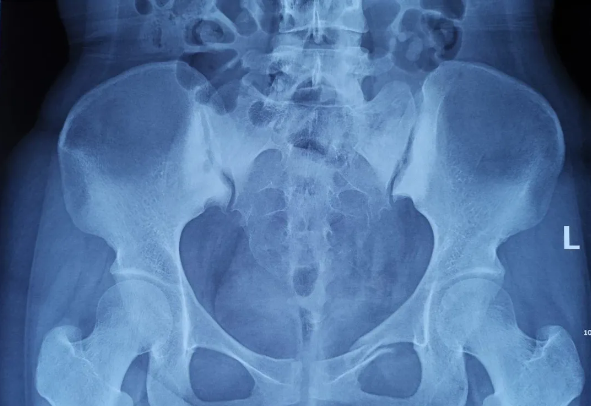

2025-02-28智匯天璣|高齡不是禁區(qū)!北京積水潭醫(yī)院智能骨科機(jī)器人助力90歲骨盆骨折患者重獲行走

由北京積水潭醫(yī)院院長蔣協(xié)遠(yuǎn)、智能骨科研究型病房主任王軍強(qiáng)帶領(lǐng)的智能骨科團(tuán)隊(duì),運(yùn)用骨科機(jī)器人輔助經(jīng)皮骨盆通道螺釘置入技術(shù),成功救治了一名90歲高齡的骨盆骨折患者。 -

2021-01-06天璣骨科手術(shù)機(jī)器人落戶南昌市第一醫(yī)院,助力骨盆骨折閉合復(fù)位內(nèi)固定術(shù)順利完成

近日,天璣?骨科手術(shù)機(jī)器人落戶南昌市第一醫(yī)院,助力骨盆骨折閉合復(fù)位內(nèi)固定術(shù)順利完成。作為江西省首先采用5G引導(dǎo)下的骨科機(jī)器人手術(shù),天璣?骨科手術(shù)機(jī)器人用它的“透視眼”,以三維影像掃描進(jìn)行深層三維空間精準(zhǔn)定位,為患者“量身定做”了最理想、最安全的教科書般通道,完成了復(fù)雜骨盆骨折微創(chuàng)治療一次性完美置釘及腰椎骨折微創(chuàng)經(jīng)皮置釘?shù)氖仔悖蔀榻魇」强瓢l(fā)展的標(biāo)志性事件,同時(shí)也是江西省骨科步入新型數(shù)字智慧骨科時(shí)代的重要里程碑事件。 -